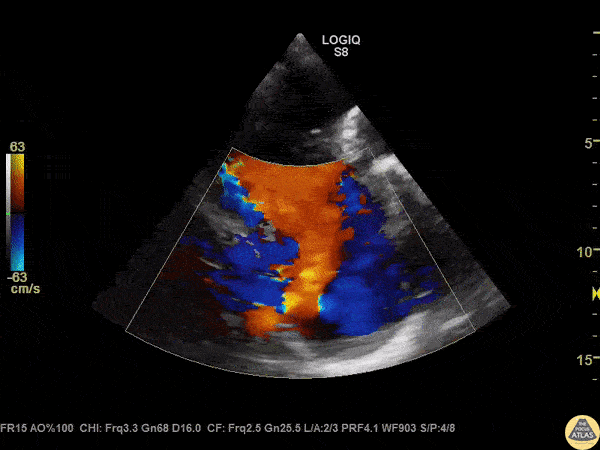

A patient with IVC and hepatic congestion on CT also had a holosystolic murmur at the left lower sternal border, worsened with inhalation. POCUS revealed severe tricuspid regurgitation on parasternal short axis view with color doppler. Image courtesy of Robert Jones DO, FACEP @RJonesSonoEM Director, Emergency Ultrasound; MetroHealth Medical Center; Professor, Case Western Reserve Medical School, Cleveland, OH View his original post here